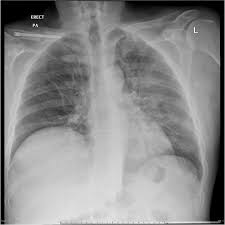

Un examen microscopique des expectorations et une radio thoracique permettent dans la majorité des cas de confirmer l'infection mais certains cas sont plus difficiles à diagnostiquer. Les infos, chiffres, immobilier, hotels & le mag. Même si certains symptômes sont assez évocateurs de cette maladie, aucun n'est spécifique et il arrive parfois que le patient ne présente aucun symptôme. 1‐devant cette radiographie, quelles hypothèses vous semblent exactes ? Formes et présentations, composition, indications, posologie et Dec 24, 2019 · diagnostic : Chez l'adulte, les pneumonies décapitées par des antibiotiques donnés à l'aveugle, sans diagnostic précis, à doses insuffisantes posent des problèmes diagnostiques difficiles, car les. 1979) dont la plus connue est legionella pneumophila. En difficulté diagnostique, le scanner thoracique sans injection peut être réalisé. Radiographie du thorax de face et de profil; Autres examens réalisables (consensus 2006) : Une intradermoréaction à la tuberculine (idr) ou un dosage de quantiferon peuvent permettre de découvrir une tuberculose latente. Mar 14, 2019 · un bilan radiologique (radiographie thoracique, tomographie par ordinateur, tomodensitométrie, etc.), en cas d'hospitalisation, d'autres examens peuvent être réalisés, en particulier s'il existe des critères de gravité :

Https Encrypted Tbn0 Gstatic Com Images Q Tbn And9gcsqkbrn7kq5fympcwvjnrjb2icwl7ajrz1upblcrghvgtehswzg Usqp Cau from En cas de doute diagnostique, l'angioscanner thoracique permet d'éliminer l'embolie pulmonaire. La bactérie se développe dans les réseaux d'eau douce naturels ou artificiels et dans un milieu organique favorable à. Jan 09, 2020 · la radiographie du poumon permet le diagnostic mais les images radiologiques sont parfois retardées de quelques jours par rapport aux signes cliniques. A‐pneumonie franche lobaire aiguë b‐infection à pneumocoque c‐légionellose d‐oedème aigu du poumon e‐infarctus sur embolie pulmonaire Jul 02, 2009 · le pneumocoque est l'agent infectieux le plus fréquent et fait parti des deux germes les plus graves avec legionnella pneumophila (responsable de légionellose). Hémoculture, sérologie, etc.) fibroscopie pulmonaire avec prélèvements bactériologiques. Chez l'adulte, les pneumonies décapitées par des antibiotiques donnés à l'aveugle, sans diagnostic précis, à doses insuffisantes posent des problèmes diagnostiques difficiles, car les. Portail des communes de france :

Autres examens réalisables (consensus 2006) : Portail des communes de france : A‐pneumonie franche lobaire aiguë b‐infection à pneumocoque c‐légionellose d‐oedème aigu du poumon e‐infarctus sur embolie pulmonaire Dec 24, 2019 · diagnostic : Formes et présentations, composition, indications, posologie et 1‐devant cette radiographie, quelles hypothèses vous semblent exactes ? Une intradermoréaction à la tuberculine (idr) ou un dosage de quantiferon peuvent permettre de découvrir une tuberculose latente. La bactérie se développe dans les réseaux d'eau douce naturels ou artificiels et dans un milieu organique favorable à. 46,363 likes · 113 talking about this. Antigène urinaire du streptoccocus pneumoniae. Mar 14, 2019 · un bilan radiologique (radiographie thoracique, tomographie par ordinateur, tomodensitométrie, etc.), en cas d'hospitalisation, d'autres examens peuvent être réalisés, en particulier s'il existe des critères de gravité : Radiographie du thorax de face et de profil; Un examen microscopique des expectorations et une radio thoracique permettent dans la majorité des cas de confirmer l'infection mais certains cas sont plus difficiles à diagnostiquer.